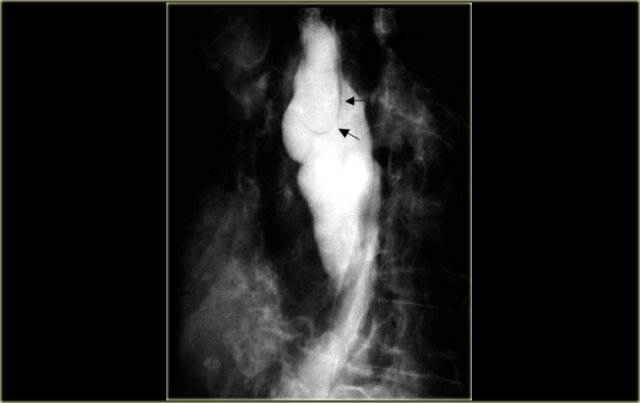

On the left a patient with a leiomyosarcoma of the esophagus.

Margin (arrows) of bulky lesion visible on chest radiograph.

Lateral view of esophagram shows marked irregularity and esophageal narrowing (arrows).

On the left another patient with a leiomyosarcoma of the esophagus.

Large lesion distorts esophageal lumen.

CT shows lesion distorting but not obstructing esophageal lumen (arrow).